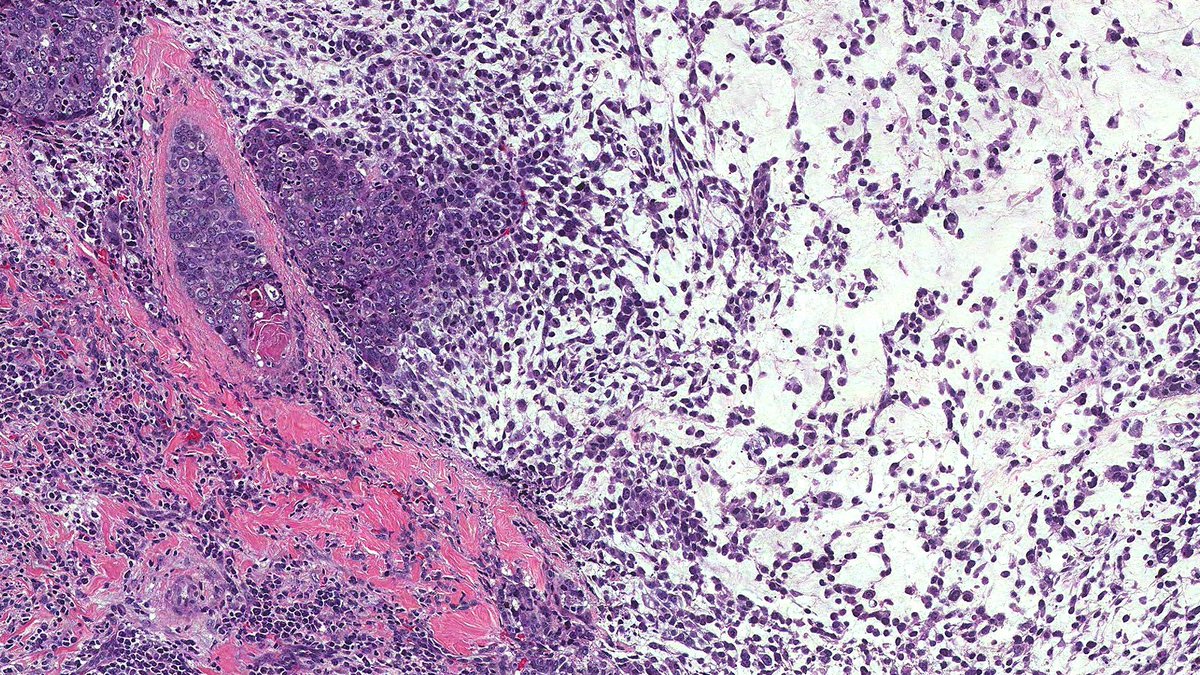

Young female with untreated HIV presents with GI bleeding and adenopathy. Which stain or stains would be the most useful to determine the cause of her symptoms? Pictures: Colon Bx, Mesenteric lymph node, Omentum #GIpath #pathology